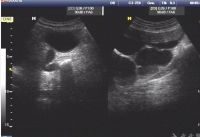

诊断肾积水的诊断一般不困难,B超是首选检查,必要时可行CT或MRI检查以便更加明确相关问题。除确定肾积水存在及程度,还应弄清楚引起积水的病因、梗阻部位、有无感染及肾功能损害情况。

对肾积水的诊断非常重要,包括B超、泌尿系统平片、尿路造影、MRI 及CT 检查等。 1.B超可以明确判定增大的肾是实性肿块还是肾积水,并可确定肾积水的程度和肾皮质萎缩情况,简便易行无创伤,应作为首选的检查方法。但对肾外壶腹型肾孟和多发性肾囊肿,有时不易与肾积水鉴别。